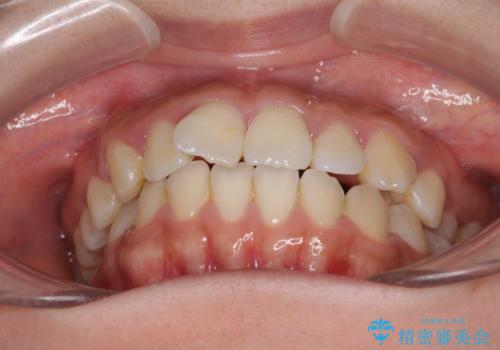

軽微な歯列不正をワイヤー矯正で整える

- 上顎歯列と下顎前歯の叢生を気にして来院された患者様です。

上顎からワイヤー矯正を開始し、終了間際から下顎前歯の叢生解消するよう計画しました。

部分矯正でしたが、咬み合わせに違和感が出ることなく気になる部分を改善させることができました。